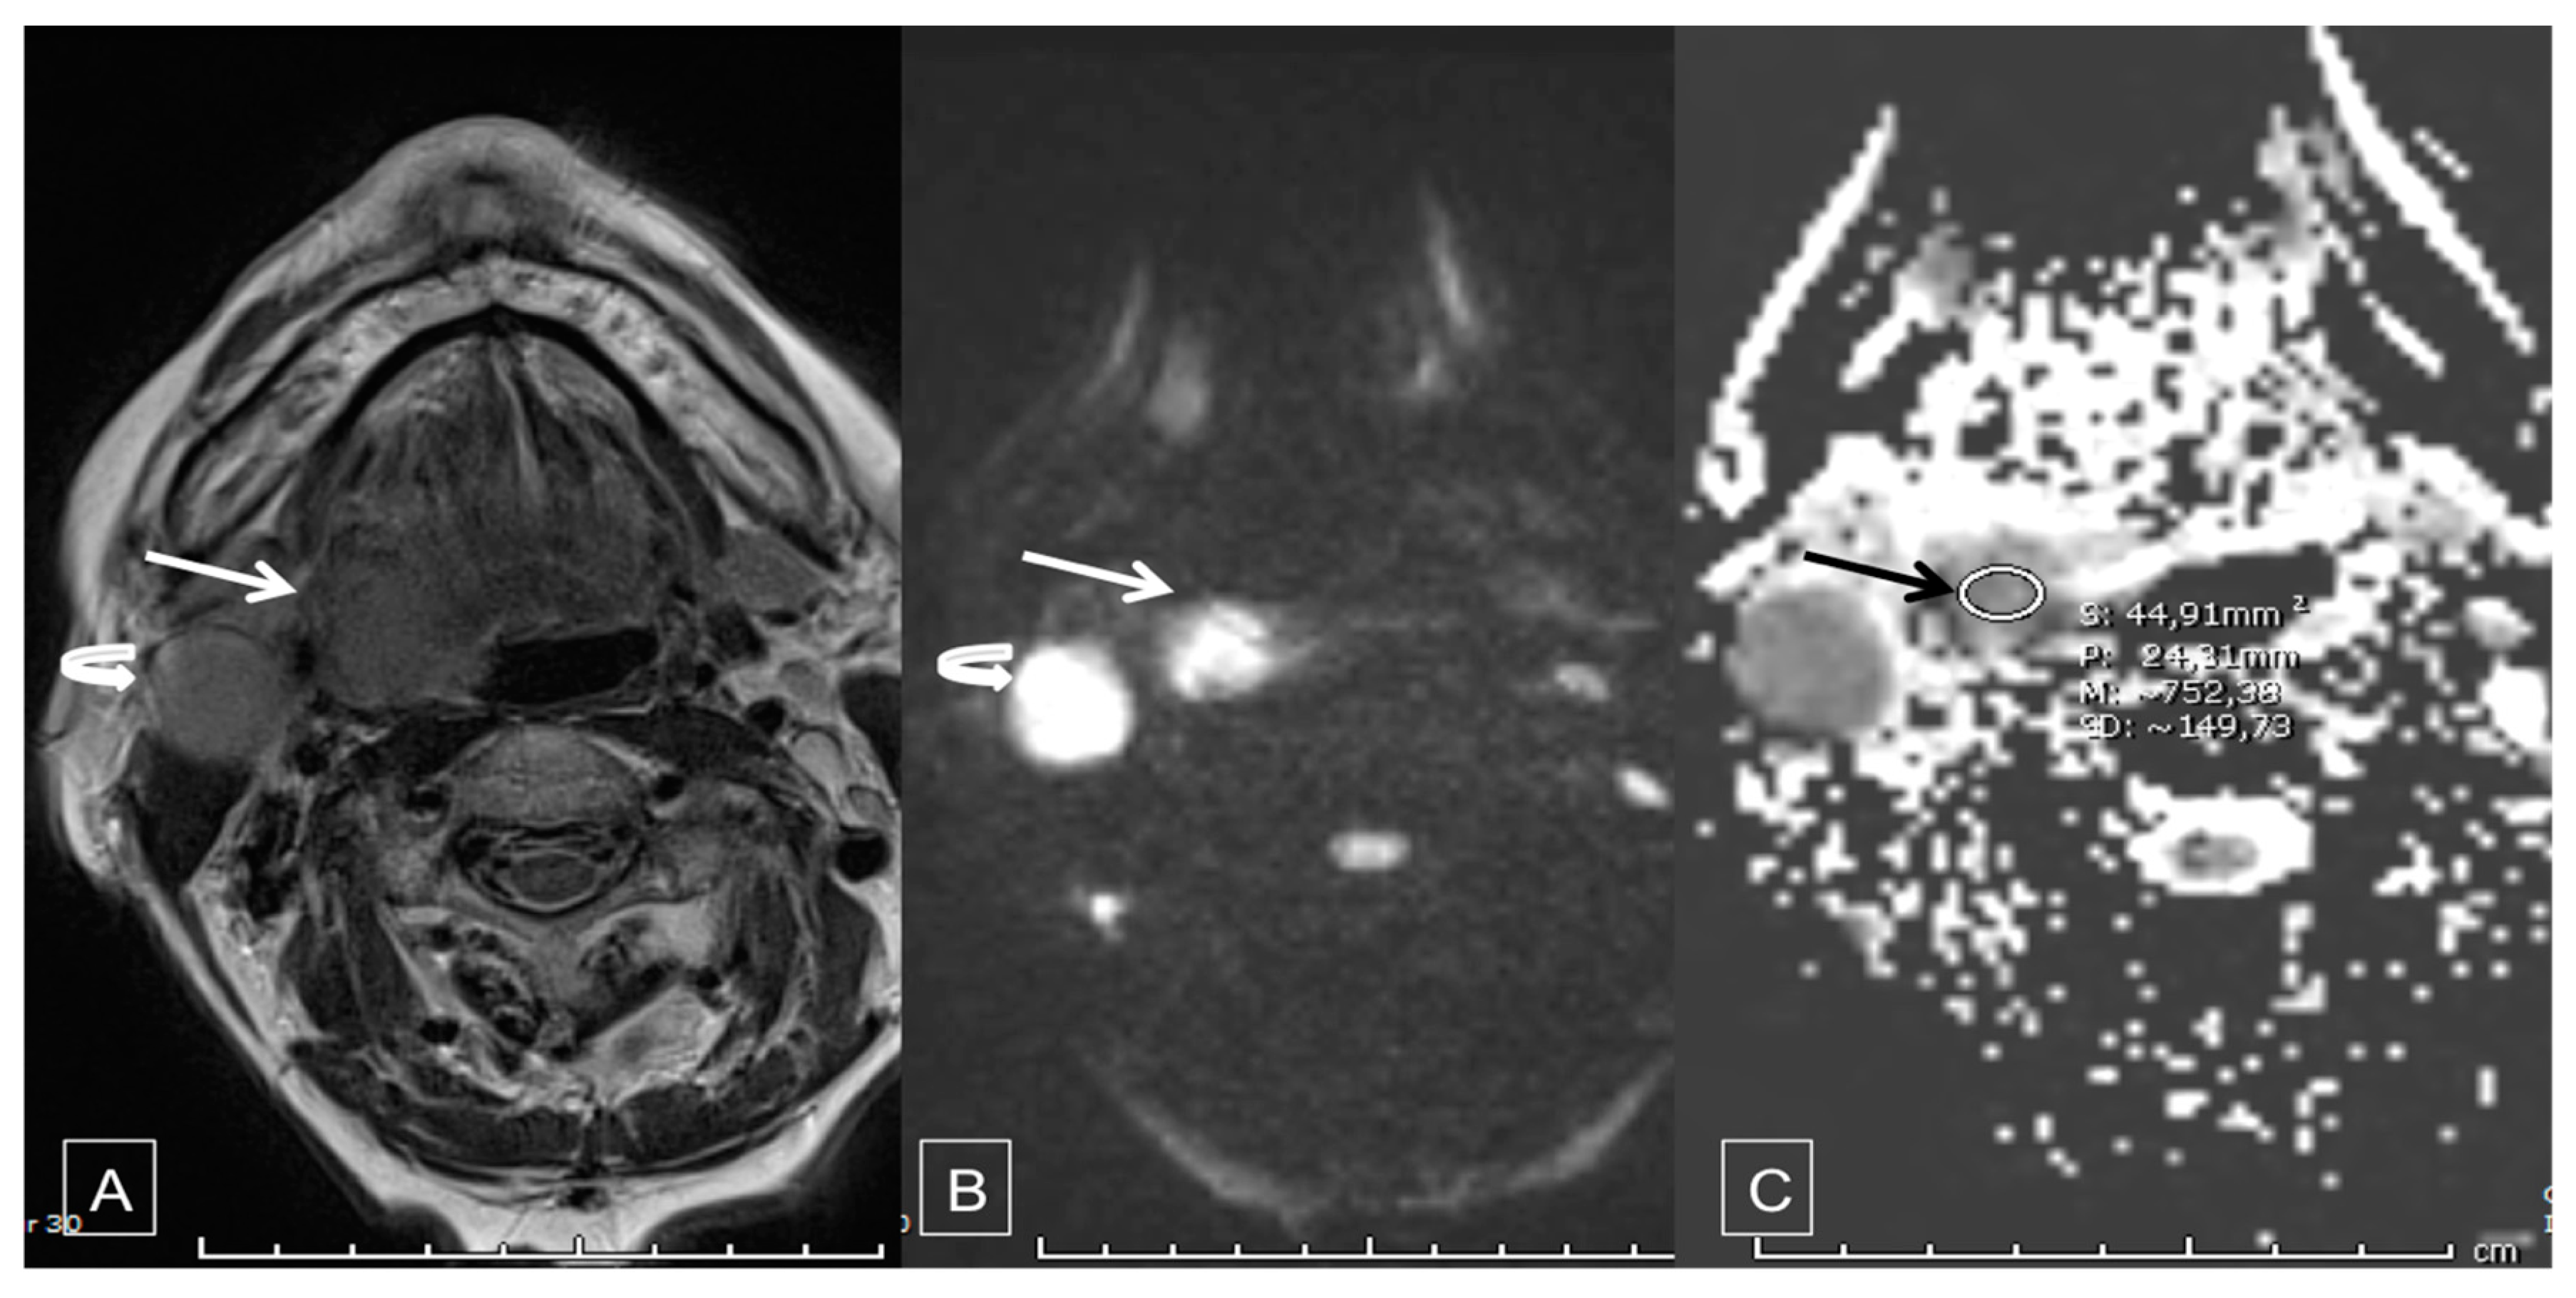

| Median ADC tumor (s/mm2) − Mean ± SD | 0.79 ± 0.13 | 0.56 ± 0.11 | <0.0001 | |||

| Patients with ADC tumor ≥0.7 | 24 (88.9) | 5 (26.3) | <0.0001 | 22.6 [4.9–103.6] | <0.0001 | |

| <0.7 | 3 (11.1) | 14 (73.7) | ||||